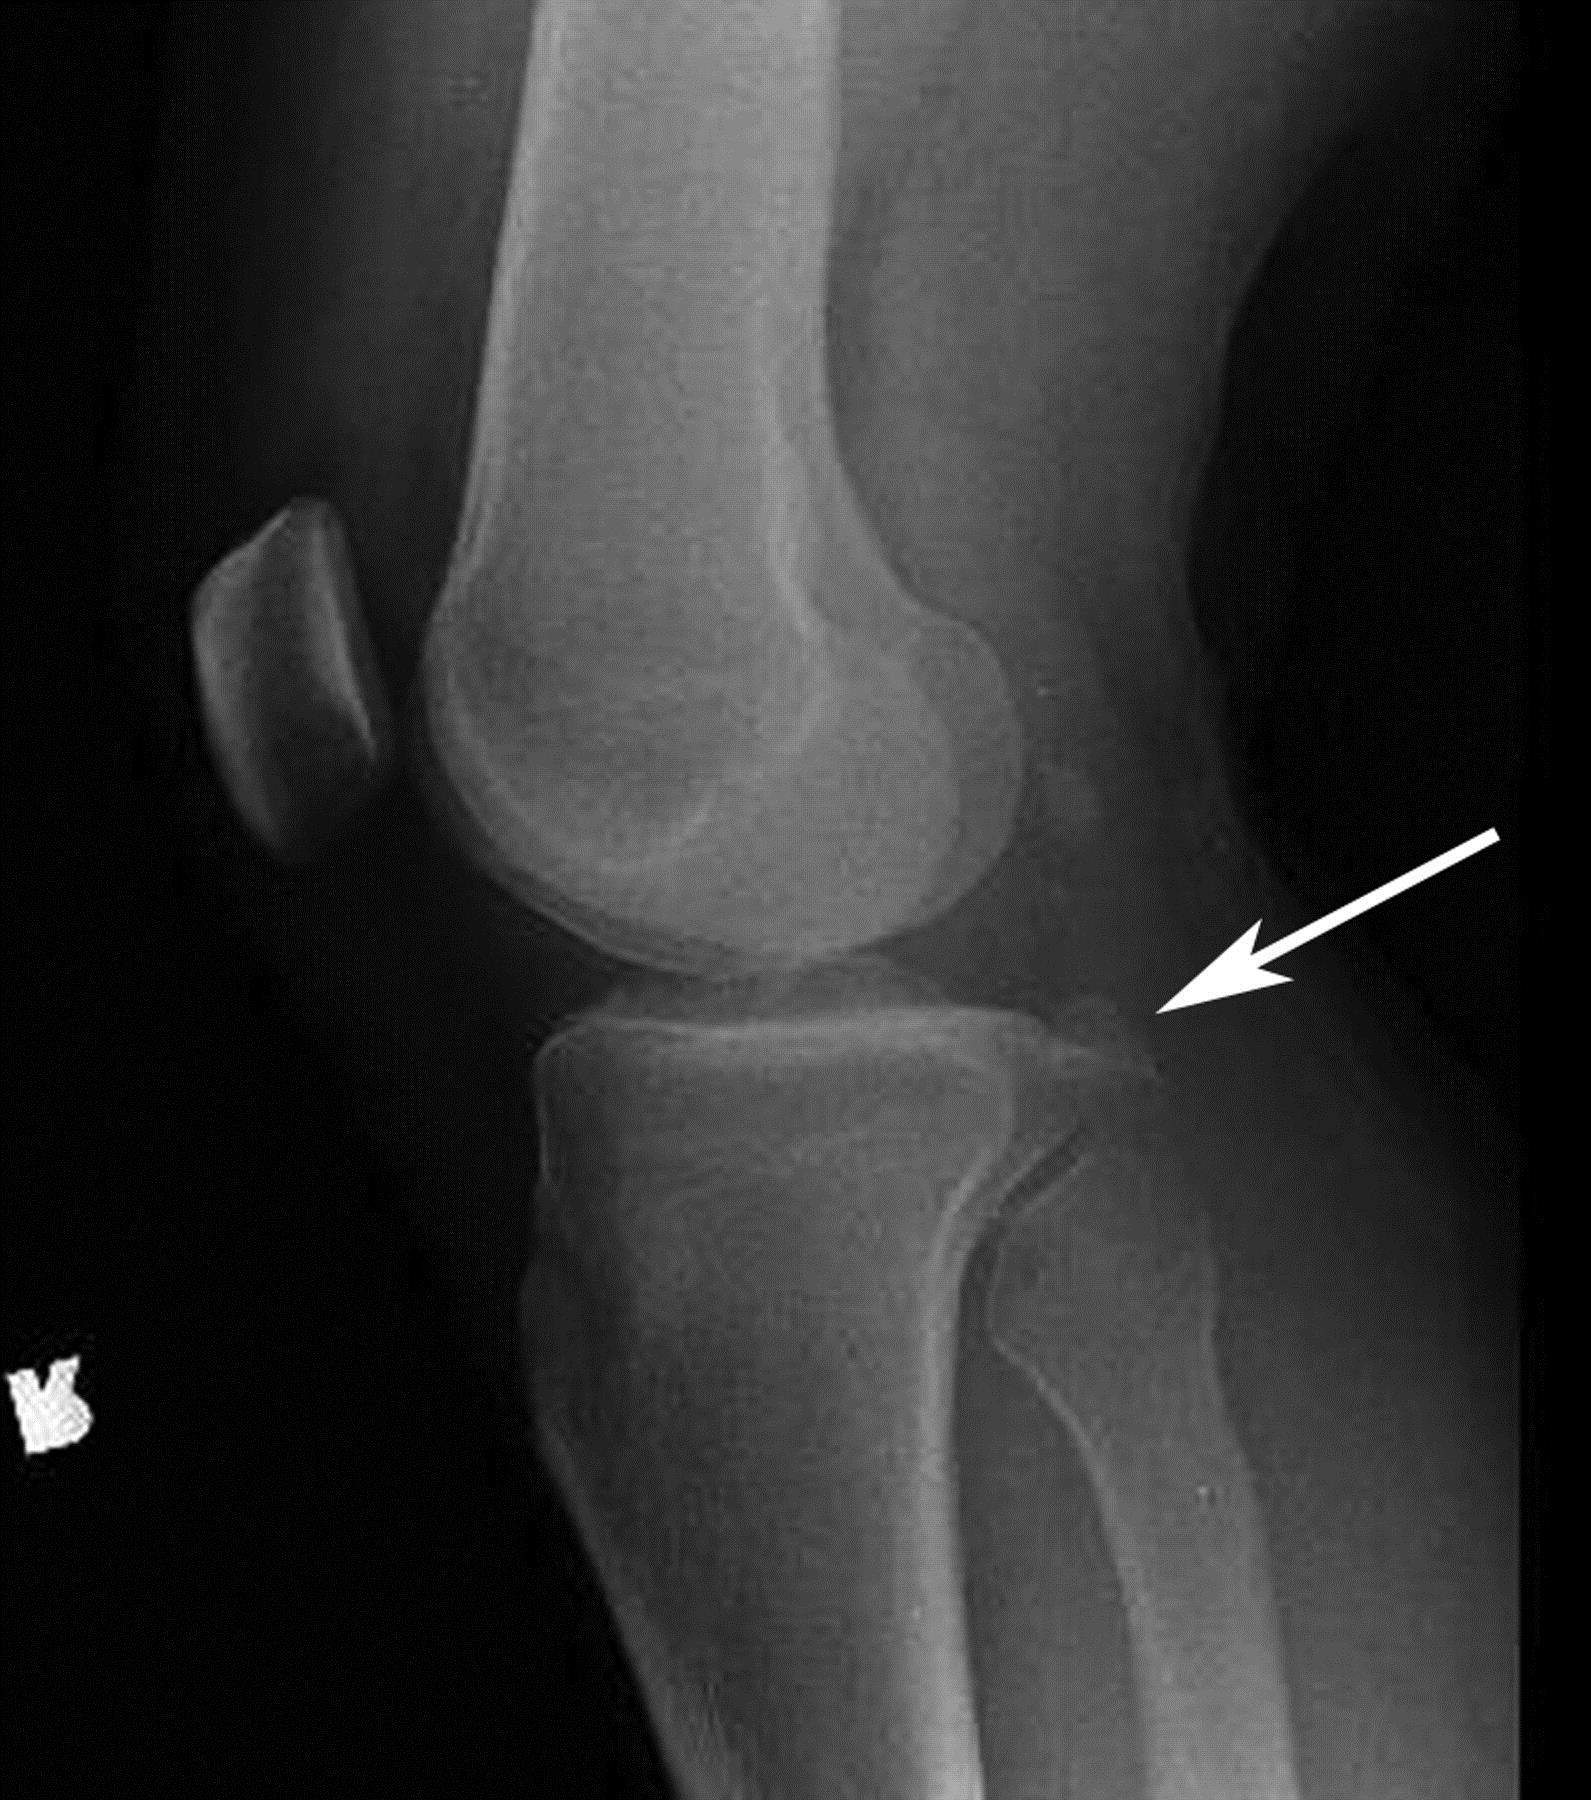

Перелом большой берцовой кости - серьезное повреждение, сопровождающееся болезненными ощущениями и нарушением функции ноги. На этой странице вы найдете много фотографий, позволяющих вам более детально изучить эту травму.

Большеберцовая кость рентген

Медицинские изображения

Здесь представлены медицинские изображения переломов большой берцовой кости, сделанные врачами в процессе диагностики и лечения. Вы сможете увидеть, как выглядит этот тип травмы на рентгеновских снимках и других медицинских изображениях.